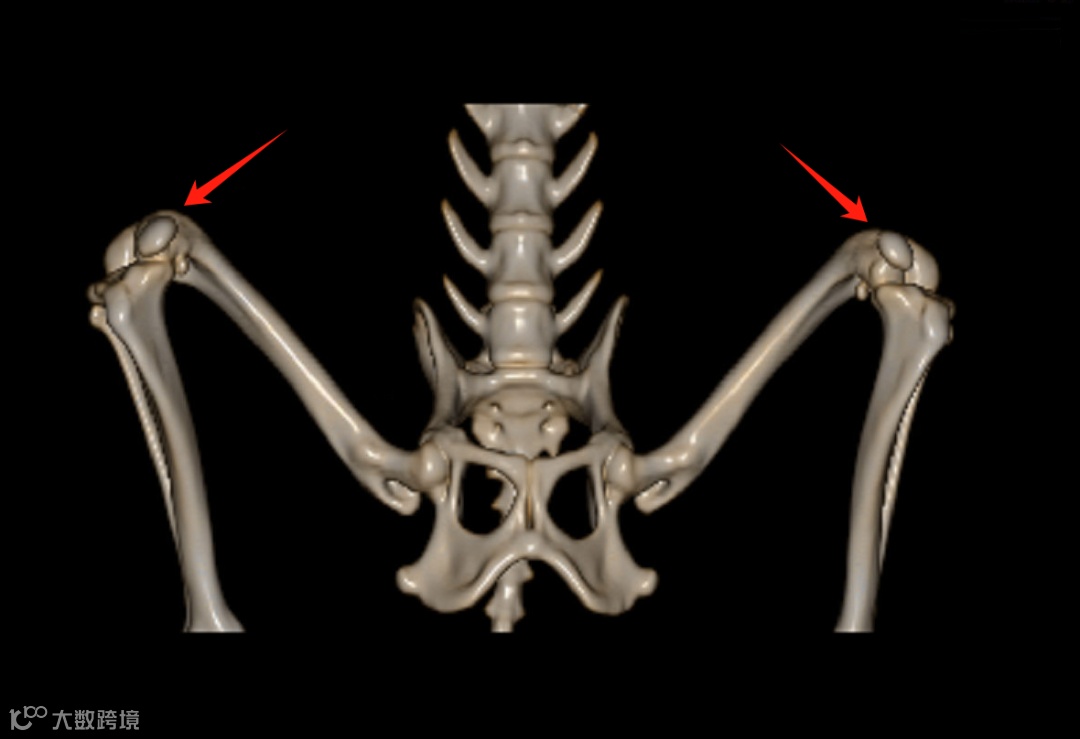

偶尔性右前肢跛行,右肩关节小游离体。